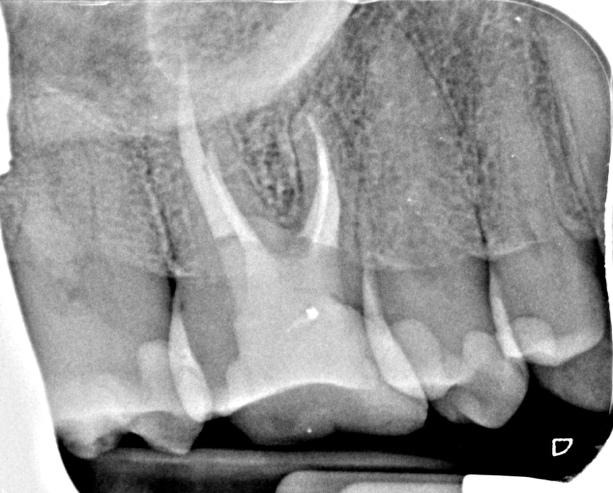

CBCT imaging allowed me to determine the size of the broken instrument, its exact location and the significance of mb2. As the instrument fragment was quite large the evidence suggests it was likely to take longer to remove so this was factored into the patient’s consent document. The patient was also advised that if I could not retrieve the instrument then a bypass strategy would be attempted either directly or via the mb2. Once the tooth was accessed, GP removal was completed with Reciproc Blue R25 file and various US attachments. I managed to bypass this instrument without too much difficulty. Following that I managed to get the broken instrument fragment ‘dancing’ using the TFRK US tips and then retrieved it with a BTR loupe pen. The re-root treatment of this tooth then became routine and was completed over 2 visits, utilising calcium hydroxide as an inter visit medicament. Following thorough disinfection, the case was obturated using hydraulic condensation and Totalfill BC sealer Hiflow and finished with a composite core with cuspal coverage recommended by the RD.

Post-op IOPA’s including a distal cone shift